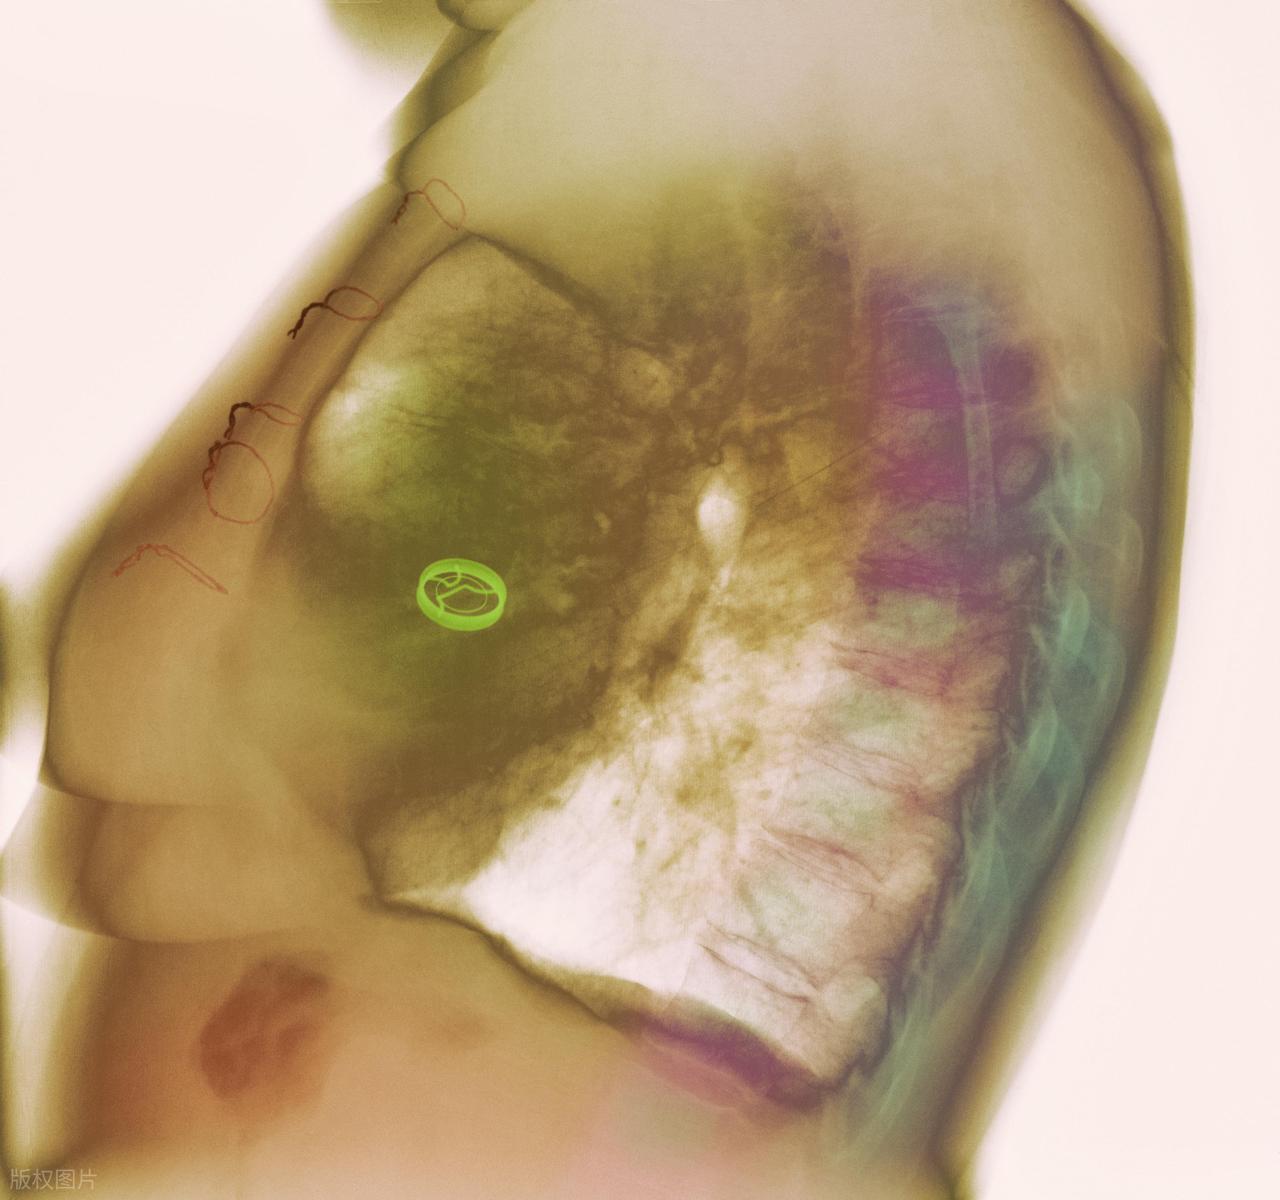

第二類:乳腺組織緻密的女性。

有的妹子雖然胸型不算大,但做鉬靶後發現影像“白濛濛”的,那就是乳腺緻密。緻密乳腺既會掩蓋腫塊,也本身與較高風險有關。林阿姨去年體檢時被告知乳腺密度高,醫生給她加做了MRI,結果發現一顆直徑僅5毫米的小結節,及時手術,避免了更嚴重的後果。